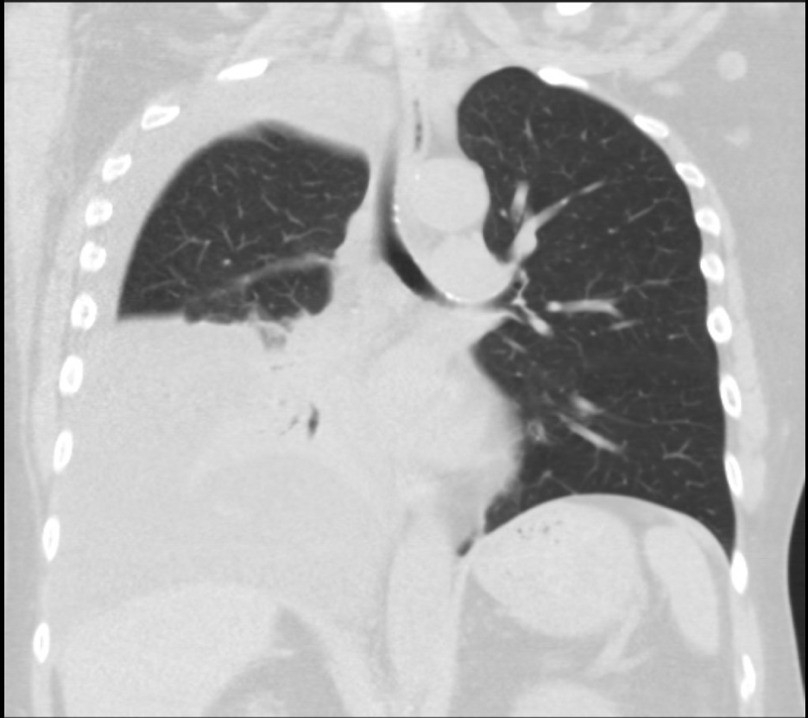

Imaging during trauma evaluation incidentally revealed a large right-sided pleural effusion with the collapse of the right mid and lower lung (Figure 1). Thoracentesis was performed with pleural fluid notable for pH 7.5, elevated glucose of 290 mg/dL, and undetectable protein and LDH, indicating a transudative effusion by Light’s criteria (Table 1). Serum glucose at the time was 128 mg/dL. A pleuroperitoneal leak was diagnosed. Peritoneal dialysis was continued with low volume exchanges with improvement in symptoms of fatigue and poor appetite as well as improved blood pressure control; however, the leak persisted after two months, and transition to HD was performed with a plan for future attempts to return to PD.

Hydrothorax is a rare complication of peritoneal dialysis that typically presents with dyspnea, pleuritic chest pain, dullness to percussion, and hypoxemia. This patient presented without such expected features of hydrothorax but was diagnosed based on incidental findings consistent with pleural effusion on the chest radiograph and subsequent thoracentesis. Some authors have reported that as many as 25% of hydrothorax patients may be asymptomatic, but the exact proportion of PD-associated hydrothorax cases that present asymptomatically is unclear.1,2